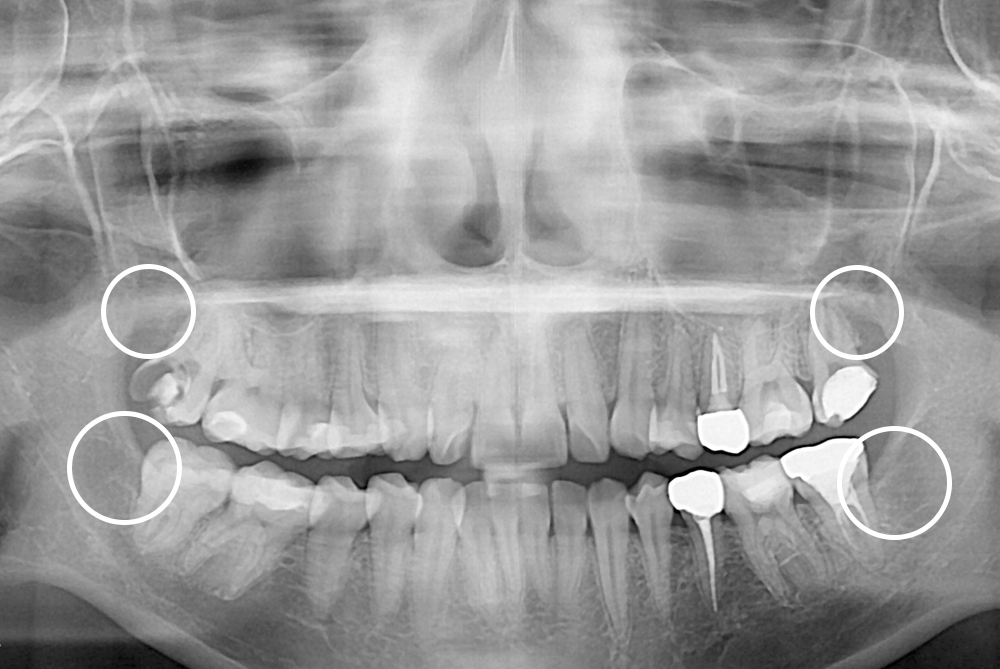

[사랑니] 매복 사랑니 발치

치료전 : 2016-12-12

세종치과는 구강악안면외과학 박사이신 원장님이 발치하는 치과입니다.